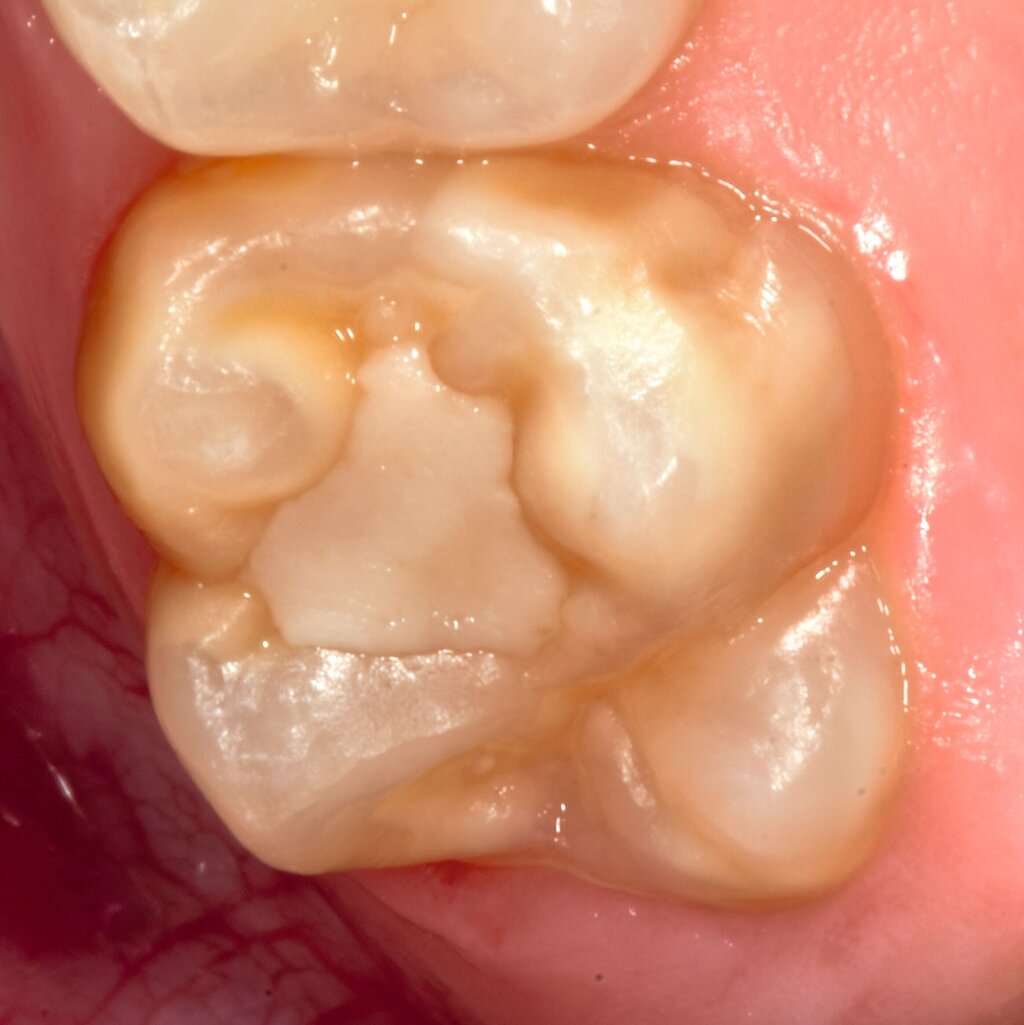

Bei post- beziehungsweise präeruptiven Oberflächendefekten ergibt sich in einigen Fällen die Indikation zur Restauration dieser MIH-Zähne. Unter Verweis auf die Lokalisation von MIH-bedingten Hypomineralisationen außerhalb der typischen Kariesprädilektionsstellen – zum Beispiel okklusale Fissuren und Grübchen oder Approximalflächen – werden diese als „atypische Restaurationen“ (engl.: „atypical restoration“, Abbildung 6) klassifiziert. Als ein weiteres Erkennungsmerkmal gilt die Präsenz von Hypomineralisationen im Bereich der Restaurationsränder. MIH- und kariesbedingte Restaurationen können und sollten sicher voneinander abgegrenzt werden.

Für die Dokumentation und Klassifikation der MIH wurden verschiedene Systeme vorgeschlagen. Als historisch und veraltet gilt der (modifizierte) DDE-Index. Demgegenüber haben die Kriterien der EAPD – abgegrenzte Opazitäten (Abbildung 3 und 4), Schmelzeinbrüche (Abbildung 5), atypische Restaurationen (Abbildung 6) – mittlerweile die weiteste Verbreitung gefunden. Diese wurden 2003 erstmals zur Beschreibung der MIH auf empirischer Basis publiziert [Weerheijm et al., 2003] und den Jahren 2010 und 2022 im Rahmen der damaligen MIH-Workshops bestätigt [Lygidakis et al., 2010; 2022].